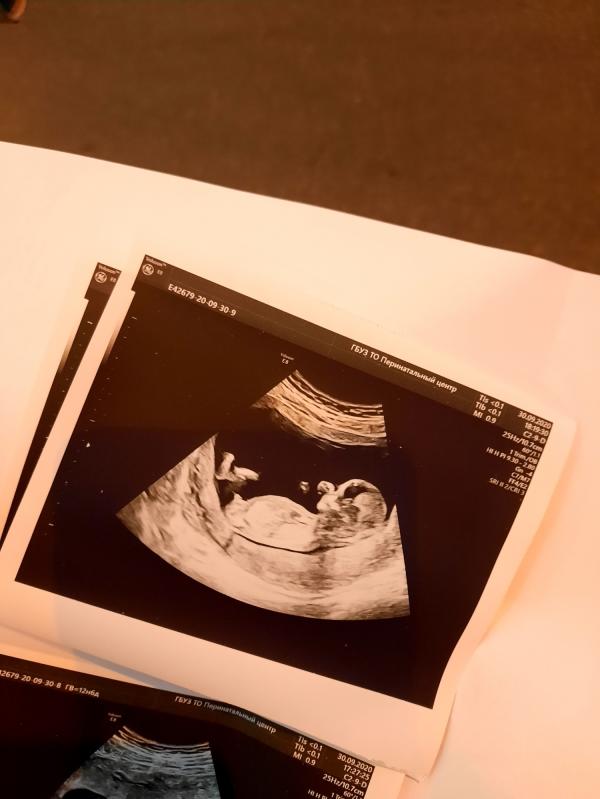

Девочки покидайте фото своих узи 13 недель пожалуйста и пол какой у вас😊 вот наши фото, на узии сначала предположили девочку, потом говорит мальчик) добавила что рано что то говорить на 100%

Ну судя по первой фотке мужичок. У моего такое же УЗИ было. Не могу на телефоне найти эту фотографию.